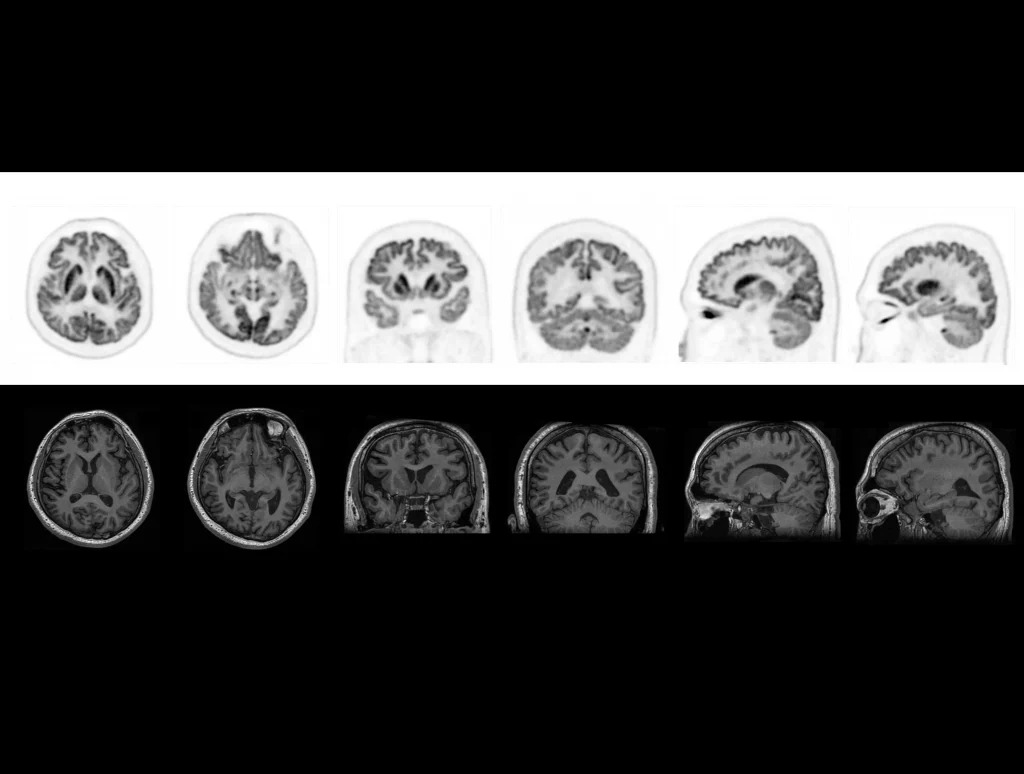

Embrace a brand-new PET/CT imaging era of enhanced confidence in decision making, streamlined workflows, and expanded research opportunities with an ultra-high resolution digital PET/CT: uMI Panorama, powered by uExcel technology platform.

uMI Panorama is clearly magnificent in every direction with the finest National Electrical Manufactures Association (NEMA) PET spatial resolution, truly-fast 189-picosecond (ps) time of flight (TOF), scalable axial field of view (AFOV), the 76-cm super-wide bore and 318-kg (700-lb) table weight capacity that accommodates patients of all sizes.1 By leveraging the AI-powered features on the uExcel platform, it also boosts your daily work efficiency significantly and opens up new possibilities for your exploration.

You can confidently set a higher standard for any image before the first moment you experience uMI Panorama. It is born to redefine your expectations for precision, with the power of the uExcel UDP (Ultra Digital Platform) detector.

The uExcel technology platform was born with its innovative designs and versatile applications in response to your clinical and research needs. Comprising the Ultra Digital Platform (UDP) detector, the intelligent scanning toolset uExcel SCAN, the AI reconstruction engine uExcel CARE, the efficient quality control system uExcel QA and the research aid uExcel EXPLORE, this platform aims to empower you to truly excel in exploring clinical panoramas with ease and innovation.